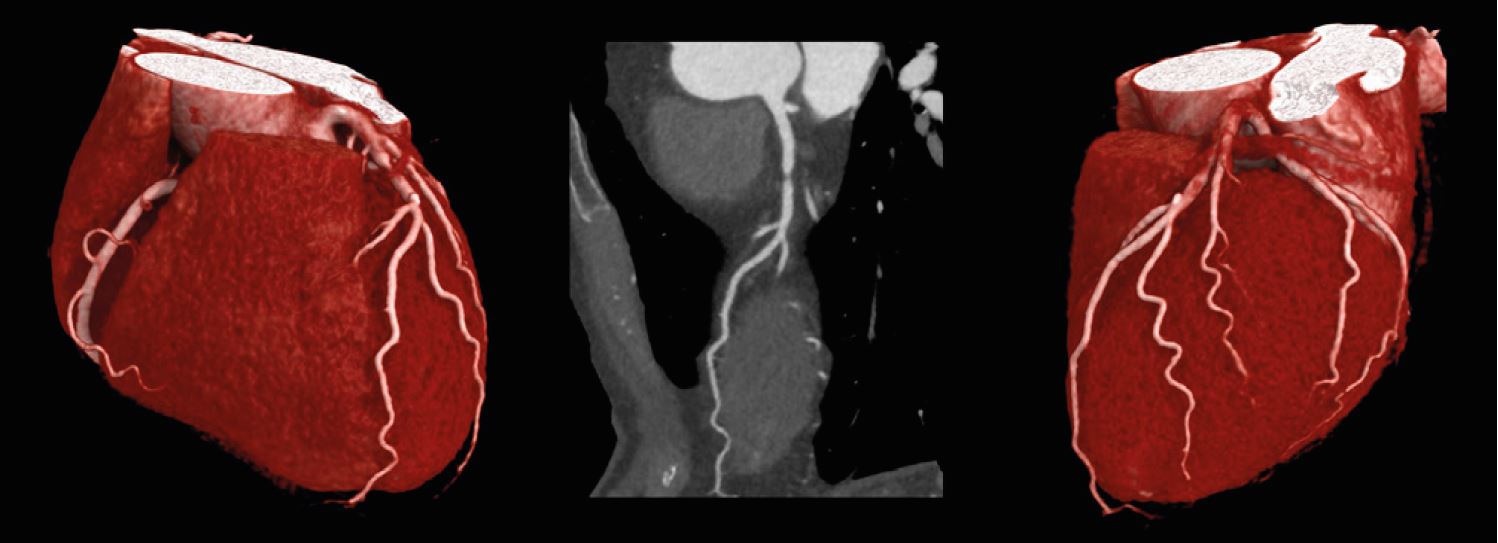

КT ангіографія серця зі стенозом проксимального відділу LAD.